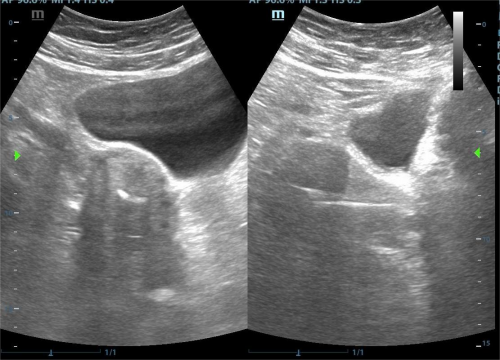

传统取环术依赖术者经验与手感,在应对节育环嵌顿、移位、断裂或绝经后宫颈萎缩等情况时,常因无法准确判断环的位置而导致失败。超声引导技术通过实时动态显示宫腔结构、节育环形态及器械位置,使术者能够精准定位环的具体位置,并引导器械沿正确方向操作,从而大幅提高取环成功率。即使是节育环断裂、残留等复杂情况,超声引导也能通过精准定位实现完整取出。

传统取环因属“盲目操作”,容易引发子宫穿孔、宫颈撕裂及出血等并发症。超声引导通过“可视化”监控器械进入的深度与方向,有效避免器械过度深入或误穿子宫壁;同时能清晰显示节育环与周围组织的关系(如是否嵌入肌层),减少因强行牵拉造成的组织损伤。

3.节育环嵌顿或断裂:超声能显示环的嵌入深度与断裂部分,指导器械精准取出;